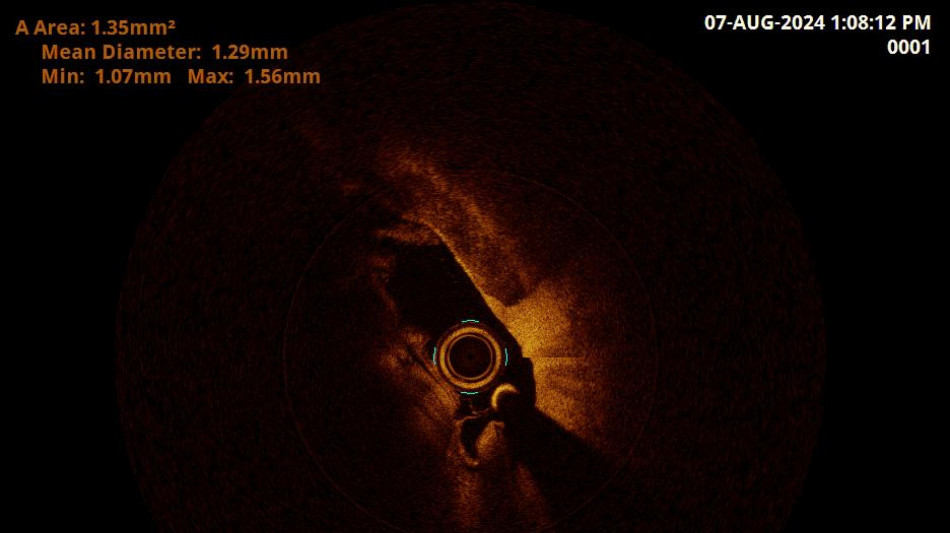

Una nuova tecnica diagnostica applicata all'ospedale Misericordia di Grosseto su un paziente che presentava sintomi di tipo confusionale ha permesso di effettuare un esame unico in Italia, ovvero una Oct (Optical coherence tomography) in un'arteria vertebrale. Una tecnica innovativa, spiega l'Asl Toscana Sud est, che ha consentito di ottenere un risultato diagnostico di grande interesse. Si tratta di una modalità che viene adottata di norma per gli esami delle arterie coronariche, ma che è risultata particolarmente efficace anche per l'arteria vertebrale. Il caso esaminato, che sarà oggetto anche di pubblicazione scientifica, ha riguardato un 70enne con sintomi simili allo svenimento e allo stato confusionale, già sottoposto ad AngioTac ed Ecocolor Doppler. Il paziente necessitava di un affinamento diagnostico ulteriore. Attraverso questo esame è stato possibile ottenere immagini ad altissima definizione, con un video a tre dimensioni dell'arteria utile a ricercare lesioni derivanti da placche da mettere in correlazione con la sintomatologia clinica. "Il caso studiato a Grosseto - commenta Massimo Pieraccini, direttore della Radiologia interventistica dell'ospedale Misericordia - evidenzia l'importanza della ricerca che portiamo avanti nel nostro ospedale e l'approccio multidisciplinare della nostra azione". "Siamo riusciti a portare il dispositivo all'interno dell'arteria vertebrale, superando molte difficoltà", spiega il neuroradiologo interventista Valerio Lunghi che ha eseguito la procedura. "L'implementazione di questa nuova metodica - dichiara Manuele Bartalucci, medico della Neurologia di Grosseto - ci ha permesso di prevenire l'insorgere dell'ictus, il tutto è avvenuto con la sinergia dei colleghi del Pronto soccorso che ci danno la possibilità di effettuare ricoveri brevi. Da inizio anno abbiamo gestito più di 500 percorsi 'Stroke', fibrinolisi e trattamenti endovascolari". Altri pazienti da sottoporre a questa nuova modalità interventistica sono già in programma nella lista d'attesa.